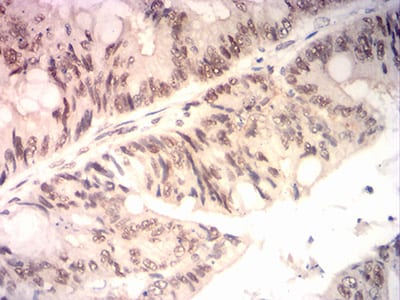

分类: 科研抗体货号: 31855别名: WDM; TIA-1应用: IHC,IF,FCM反应种属: Human